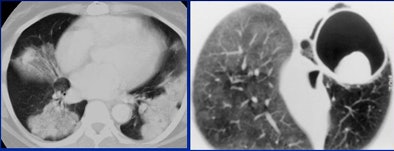

Lesions with an atypical appearance that may be lung cancers include airspace disease and ground-glass opacities, calcifications, thin-walled cavitation-bulla-associated cancers, cystic lung lesions, and the air-crescent sign.

|  |

| Consolidated bronchoalveolar cell carcinoma represents a classic atypical lesion. |